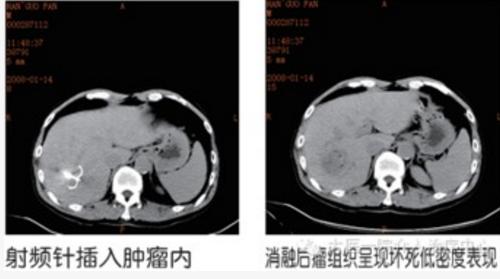

1、可以分为血管性介入技术和非血管介入技术。治疗心绞痛和急性心肌梗死的冠状动脉造影、溶栓和支架置入就是典型的血管性介入治疗技术,而肝癌、肺癌等肿瘤的经皮穿刺活检、射频消融、氩氦刀、放射性粒子植入等就属于非血管介入技术。

2、肿瘤性疾病方面:包括肿瘤的供血动脉栓塞与药物灌注、术前栓塞肿瘤血管、肿瘤经皮穿刺活检、射频消融、冷冻消融(氩氦刀)、放射性粒子植入等。

3、非血管介入技术包括各种经皮穿刺活检术、各种非血管性腔道的成形术(包括泌尿道、消化道、呼吸道、胆道等狭窄的扩张和支架)、实体瘤局部灭能术(经皮穿刺瘤内注药术、射频消融术)、囊肿脓肿引流术、造瘘术(胃、膀胱等)、胆道结石和肾结石微创取石术、骨转移或椎体压缩骨折的椎体成形术、神经丛阻滞术治疗慢性疼痛等。